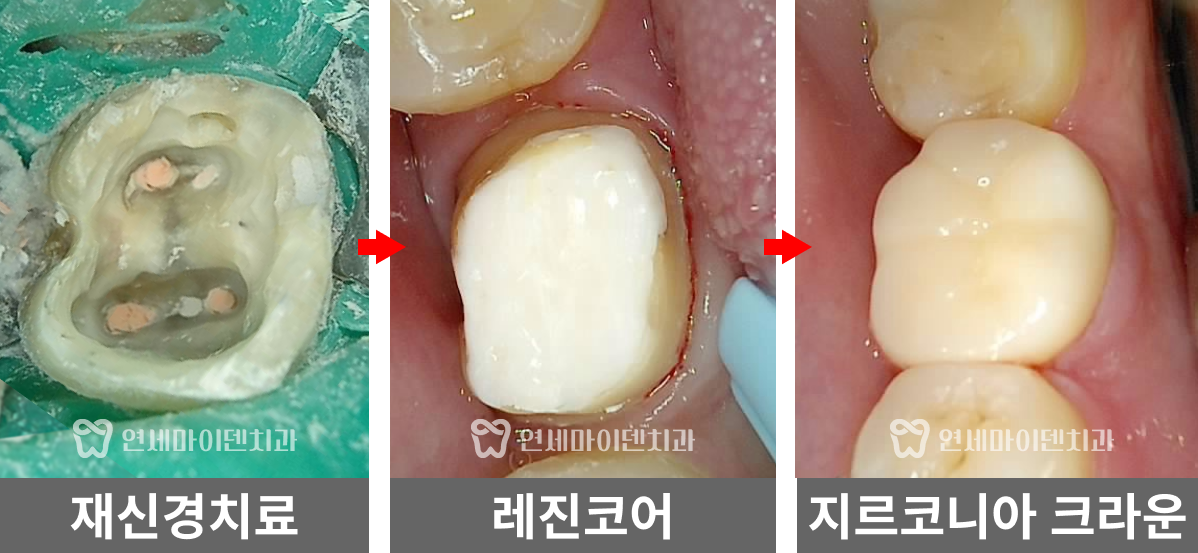

재신경치료를 위해 치아를 뜯어보니, 파란색으로 레진코어가 되어있었습니다.

*파란색은 레진의 종류인데, 과거 어금니 치료는 치아와 보철물의 색 구분을 위해 파란색으로 사용하는 경우가 많았습니다. 이렇게 해두면 나중에 재치료할 때 의사가 구분하기 편하기 때문입니다. 다만 저희처럼 현미경으로 치료하다보면, 레진을 치아색으로 덮어놔도 치아와 레진 구분이 어렵지 않기 때문에 저희는 그냥 치아색 나는 레진을 사용하고 있습니다.

그런데 레진 치료가 원칙적으로 되어 있지 않았습니다.

치아 내부에 레진이 아닌 IRM(Intermediate Restorative Material)과 ZOE(Zinc Oxide Eugenol) 같은 임시 재료가 채워져 있었고, 표면만 얇게 레진으로 덮여있었습니다.

다만 해당 임시 재료는 치아와 제대로 접착되지 않으며, 현재는 주로 임시 충전재로만 사용되기 때문에, 이런 방식은 레진 코어의 본래 목적을 달성할 수 없습니다.

예상대로 레진과 치아사이 접착이 제대로 이루어지지 않아 그 틈으로 충치가 시작된 것이었고,

환자 분의 치아 문제는 다시 원칙적인 치료로 개선할 수 있을 것이라 판단했습니다.

그리고 앞쪽 치아의 신경치료 방식을 보니 거타포차 콘(GP cone)을 하나씩 삽입하는 오래된 방식으로 이뤄져 있었습니다. 오래된 방식이라고 반드시 나쁜 것은 아닙니다. 다만 현재 훨씬 개선된 치료법이 존재하기 때문에 환자분들께서 더 완성도 높은 치료를 받으실 수 있습니다.

거타퍼차 콘(GP cone)을 하나씩 꽂는 방식이 아닌, 수직 가압 충전법을 사용하여 거타퍼차 콘을 녹여 충전하는 현대적 방식으로 진행하였습니다. 레진 충전시에도 임시 재료 없이 원칙적인 치료로 진행했습니다.